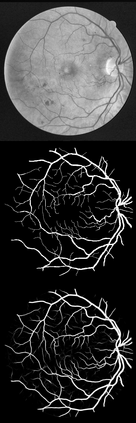

U-Net has been providing state-of-the-art performance in many medical image segmentation problems. Many modifications have been proposed for U-Net, such as attention U-Net, recurrent residual convolutional U-Net (R2-UNet), and U-Net with residual blocks or blocks with dense connections. However, all these modifications have an encoder-decoder structure with skip connections, and the number of paths for information flow is limited. We propose LadderNet in this paper, which can be viewed as a chain of multiple U-Nets. Instead of only one pair of encoder branch and decoder branch in U-Net, a LadderNet has multiple pairs of encoder-decoder branches, and has skip connections between every pair of adjacent decoder and decoder branches in each level. Inspired by the success of ResNet and R2-UNet, we use modified residual blocks where two convolutional layers in one block share the same weights. A LadderNet has more paths for information flow because of skip connections and residual blocks, and can be viewed as an ensemble of Fully Convolutional Networks (FCN). The equivalence to an ensemble of FCNs improves segmentation accuracy, while the shared weights within each residual block reduce parameter number. Semantic segmentation is essential for retinal disease detection. We tested LadderNet on two benchmark datasets for blood vessel segmentation in retinal images, and achieved superior performance over methods in the literature. The implementation is provided \url{https://github.com/juntang-zhuang/LadderNet}